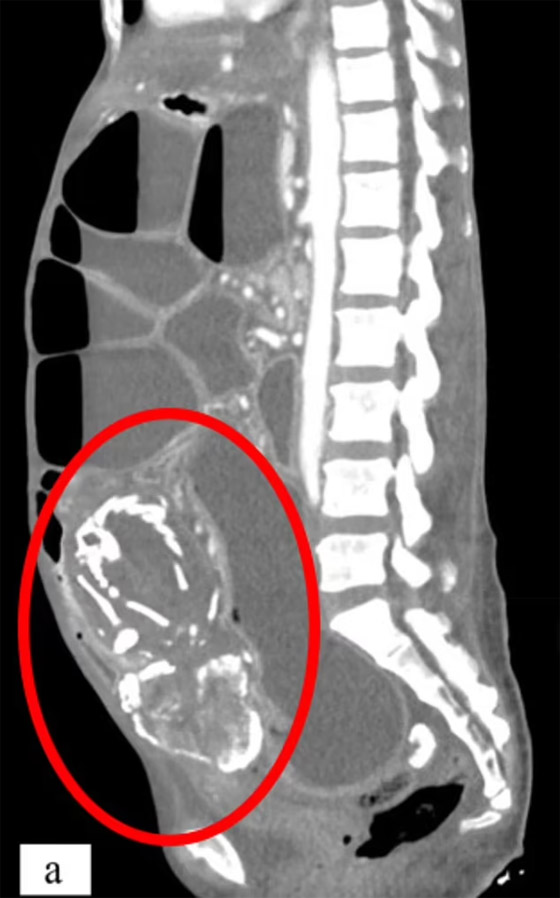

توفيت امرأة إفريقية تبلغ من العمر 50 عاما في نيويورك، بحالة نادرة بسبب وجود جنين متحجر في بطنها لمدة 9 سنوات. وزارت المرأة الأطباء في نيويورك تشكو من تقلصات في المعدة وعسر هضم وصوت غرغرة بعد تناولها للطعام. كشفت الفحوصات وجود جنين متحجر في بطنها، ضغط على أمعائها لفترة طويلة ومنعها من امتصاص الغذاء بشكل جيد ما أدى إلى وفاتها نتيجة نقص التغذية الحاد.

الظاهرة النادرة، التي تم تسجيلها حوالي 300 مرة فقط، تحدث عندما يموت الجنين الذي ينمو خارج الرحم أثناء الحمل ولا يتم إخراجه من الجسم. وقد توفيت المرأة بعد 14 شهرا من وصولها إلى الولايات المتحدة، وقال الأطباء إنها ماتت نتيجة سوء التغذية الحاد.

وقال وسيم سوس، خبير الطب الباطني في جامعة ولاية نيويورك الطبية إن المريضة رفضت التدخل الطبي خوفا من الجراحة، لسوء الحظ، توفيت بسبب سوء التغذية الحاد بعد انسداد الأمعاء المتكرر. تنقلت المرأة للعيش من الكونغو إلى بوروندي ثم تنزانيا بسبب النزاعات، استقرت في تنزانيا وأنجبت 8 أطفال ولدوا بشكل طبيعي.